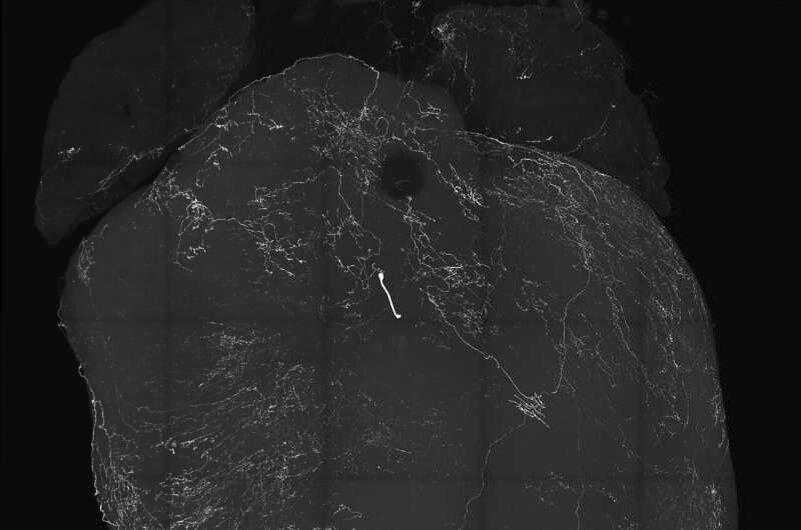

Изображение сердца, размеченное сенсорными нейронами блуждающего нерва. В новом исследовании, опубликованном в журнале Nature , исследователи из Калифорнийского университета в Сан-Диего и их коллеги обнаружили, что эти нейроны вызывают обмороки, закладывая основу для решения проблем, связанных с обмороками. Фото: Augustine Lab, Калифорнийский университет в Сан-Диего.

Исследователи из Калифорнийского университета в Сан-Диего и сотрудничающих с ним учреждений подчеркнули огромные перекрестные помехи между сердцем и нервной системой. На видео видно, как сердечная деятельность резко замедляется из-за стимуляции сенсорных нейронов блуждающего нерва, что, как выяснилось, вызывает обмороки.

Исследователи сосредоточились на генетике сенсорного кластера, известного как узловые ганглии, который является частью блуждающих нервов, передающих сигналы между мозгом и внутренними органами, включая сердце. В частности, сенсорные нейроны блуждающего нерва, или VSN, передают сигналы в ствол мозга и, как полагают, связаны с BJR и обмороками. В поисках нового нервного пути они обнаружили, что VSN, экспрессирующие нейропептид Y-рецептор Y2 (известный как NPY2R), тесно связаны с хорошо известными реакциями BJR.